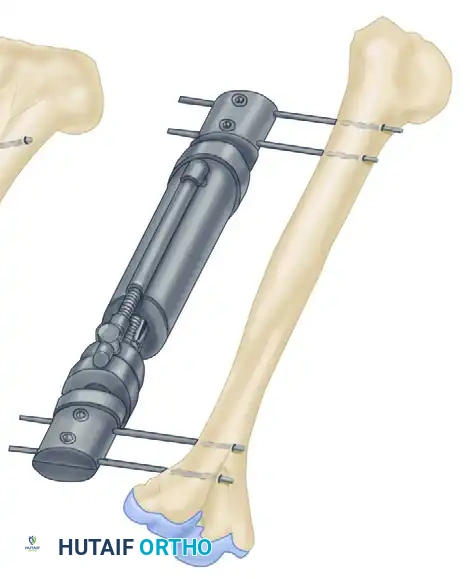

Biomechanics of External Fixation

Understanding the biomechanics of external fixation is critical for the orthopedic surgeon. The stability of the frame dictates the mechanical environment at the fracture site, which in turn influences the type of bone healing (primary vs. secondary).

Factors Influencing Frame Stiffness

The rigidity of an external fixator construct is determined by several modifiable variables:

* Pin Diameter: The stiffness of a half-pin is proportional to the fourth power of its radius ($r^4$). Increasing the pin diameter is the single most effective way to increase frame rigidity. However, pin diameter should not exceed one-third of the bone's diameter to prevent stress risers and subsequent iatrogenic fractures.

* Distance from Bone to Rod: The closer the longitudinal rod is to the bone, the stiffer the construct. The rod should be placed approximately 2 to 3 cm from the skin to allow for postoperative swelling while maximizing stability.

* Pin Spread: Increasing the distance between the two outermost pins in a single bone segment increases the stability of the construct.

* Number of Pins: Increasing the number of pins per segment increases stiffness, though the biomechanical advantage diminishes after three or four pins per segment.

* Number of Bars: Adding a second longitudinal bar (creating a stacked or double-bar construct) significantly increases stiffness, particularly in bending and torsion.

* Multiplanar Constructs: Placing pins in different planes (e.g., a delta frame or biplanar construct) dramatically increases torsional and bending rigidity compared to a uniplanar frame.